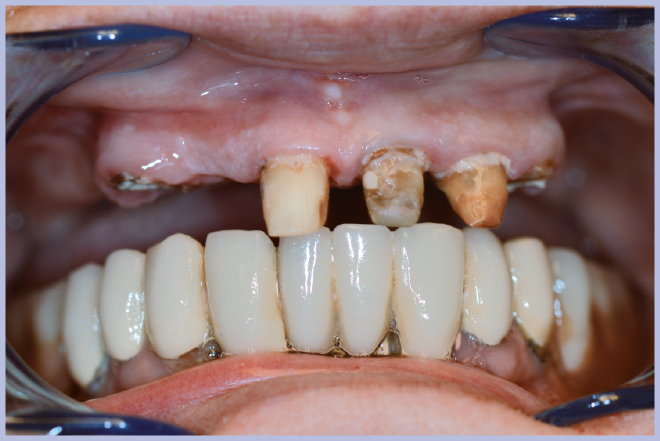

Dopo l’estrazione dei 3 elementi residui (Fig. 2), sono stati posizionati 4 impianti Max Stability Ø3,75 mm (2 di lunghezza 10 mm e 2 di lunghezza 12 mm).

- Fig. 2 – Elementi residui prima dell’estrazione